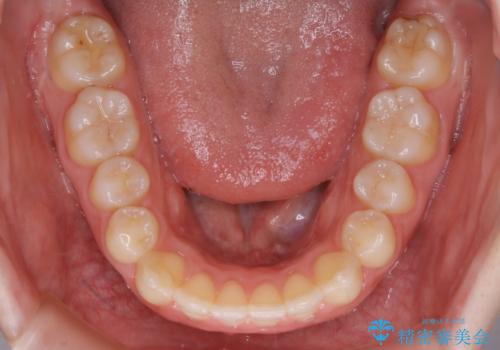

【非抜歯】上下の前歯が噛み合わないオープンバイトの治療

- 噛み合わせの不調を主訴にご来院されました。

骨格的な問題もあり、噛んだ時に奥歯しか当たらず前歯の被蓋があまりない状態でした。

奥歯を沈めて噛み込みを深くしていくことで被害の改善が起こるとともに、下顎自体が前上方に回転移動することで顔貌的にも変化を出すことができます。

臼歯の位置が高く噛んだ時に奥歯しか当たらなかったり、舌癖などが原因で前歯が前に倒れてしまうことで上下の前歯の被蓋がなくなってしまっている状態をオープンバイトといいます。

前者の場合は臼歯を圧下し沈めてあげることで改善させます。後者の場合は前方に傾斜している歯を元の角度に戻してあげることで改善しますが、舌癖がある場合はその癖自体を無くす治療をしない限りまた同じ状態へと後戻りしてしまいます。